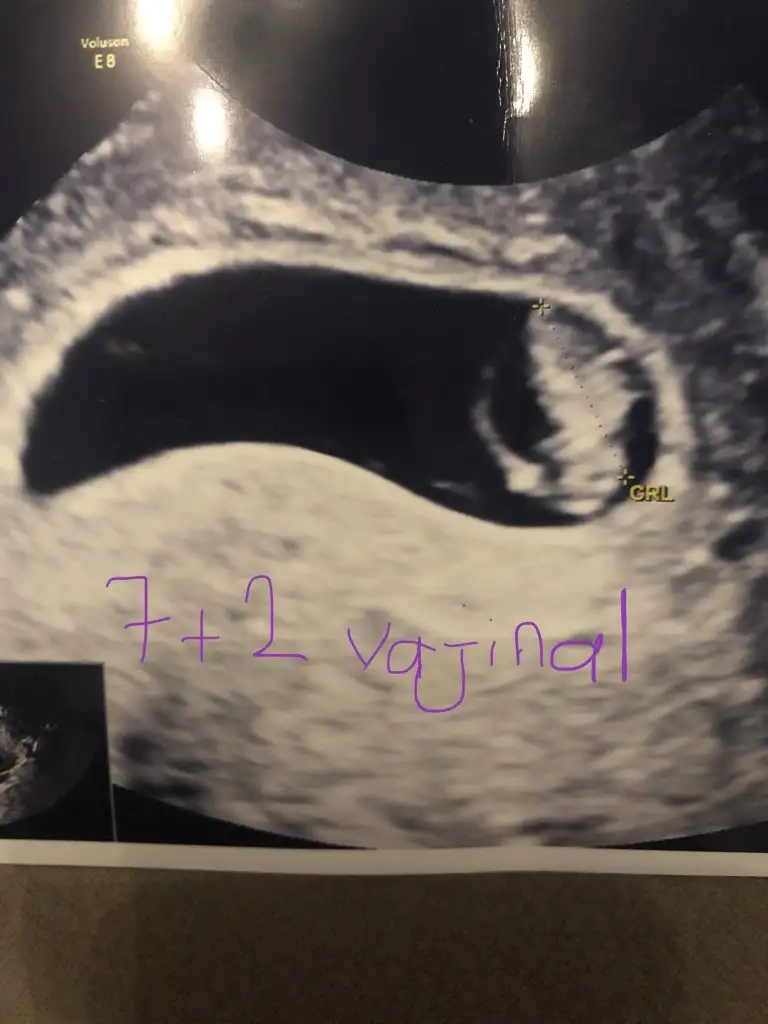

Kız sanki ama emin değilimYa benim ultrason foto da hicbirsey görünmüyor sanırımben mi göremiyorum

Ikra meyra bir fikriniz var mı acaba?

Kız gibi sanki

USG fotografinda Kaç haftalık?Teşekkürler Dr kız tahminim dedi ilerki haftalarda İnş kesin öğreniriz

Kızdır o zamanTeşekkürler Dr kız tahminim dedi ilerki haftalarda İnş kesin öğreniriz